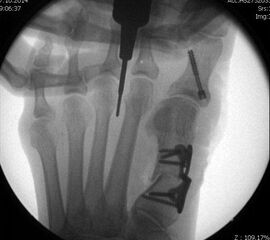

Nach Bestimmung der korrekten Osteotomiehöhe wird mit dem MIS-Mikrotom eine je nach Seitendominanz des Operateurs dorsolaterale oder dorsomediale 3-4mm lange Längsinzision parallel zu den Strecksehnen auf Höhe des metadiaphysären Überganges am distalen, zu osteotomierenden Metatarsale  durchgeführt. Im Anschluss erfolgt die Präparation mit einer schlanken, im Schaft gebogenen und vorne stumpfen Raspel oder mit einem gebogenen Klemmchen. Die Präparation erfolgt unter stetigem  Knochenkontakt mit der Kortikalis des Metatarsale medial oder lateral bis nach plantar unter die Beugesehenen.  So kann der Weg für die Fräse vorpräpariert und eine Weichteilinterposition zwischen Fräse und Knochen vermieden  werden.

Jetzt erfolgt das Einbringen der Fräse im 45°-Winkel von distal dorsal nach proximal plantar. Auf steten Knochenkontakt mit der Kortikalis zur Vermeidung eines Weichteilinterponates sollte geachtet werden. In unserer Abteilung erfolgt vor Beginn der Osteotomie nun eine nochmalige Lagekontrolle der Fräse unter dem Bildwandler im dorsoplantaren Strahlengang. Eine zusätzliche laterale Aufnahme kann die Tiefe der eingebrachten Fräse in Bezug auf das zu osteomierende Metatarsale zeigen, ebenso ermöglicht sie eine Kontrolle des 45°-Winkels.

In einer rotatorischen Bewegung mit dem Drehpunkt im Bereich der Hautinzision erfolgt nun die Osteotomie zunächst - in Abhängigkeit von der zu operierenden Seite und der Rechts- oder Linkshändigkeit des Operateurs  - des medialen bzw. lateralen Kortex des Metatarsale, gefolgt von den plantaren Anteilen und anschliessend dem gegenseitigen Kortex. Am Ende der rotatorischen Bewegung befindet sich die Fräse, die am Anfang der Osteotomie noch parallel zum Metatarsaleschaft ausgerichtet war, im 90°-Winkel zu diesem.